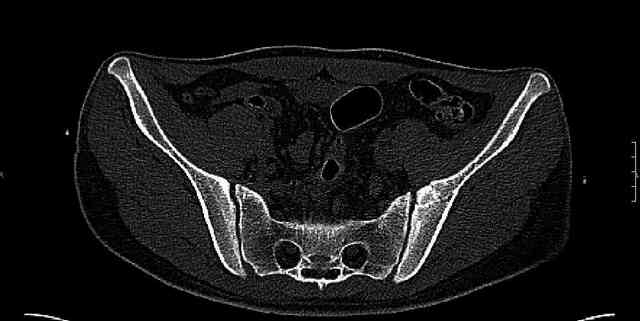

Some more images. Does it help to guess which part of the acetabulum is displaced?